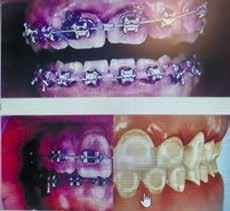

Als geregistreerd mondhygiënist

(HBO-paramedicus) ziet Marigeth

Eimers de meerwaarde voor haar patiënten die haar vakgebied brengt:

“De behandelmethoden die ik kan aanbieden, stem ik af op de patiënt en daarnaast is de apparatuur ook sterk verbeterd. Dat kan helpen om angst voor pijn te verminderen. Angst voor de behandeling bij de mondhygienist is begrijpelijk, maar een slechte raadgever voor een gezond gebit en mond.”

Heldere communicatie is voor Marigeth gewoon onderdeel van het werk. Daarmee neemt ze de patiënt stapje voor stapje mee in het behandeltraject en als ze ziet dat een tandvleesontsteking niet met één behandeling op te lossen is, geeft ze dat duidelijk aan. En dat ervaren ook haar patiënten als positief.

Preventie en lage drempel

Jouw missie is om de gang naar de mondhygiënist makkelijker te maken. Is dat nog een probleem? “Zeker. De ervaring leert dat de mondzorg makkelijk in het gedrang komt. Voornamelijk door angst en sluit ook schaamte en kosten niet uit. Ik geloof in mijn aanpak, waarin ik meerwaarde zie in samenwerking met tandartsen. Zo kun je met complete mondzorg werken aan preventie. En dat begint al bij de kinderen. Zo zie ik vaak ouders met kinderen, waarbij de ouders het erg lastig vinden om de mondhygiëne optimaal bij hun kinderen te houden. Ook veel beugelbekkies heb ik vaak in mijn stoel. Een beugel kan bij slecht onderhoud leiden tot ontkalkingsvlekken op de tanden. Alleen goed poetsen is dan echt een uitdaging en niet voldoende. Deze specifieke gevallen brengen dan vaker een bezoek, wat dan resultaat boekt.”

behandeld kan dat weer leiden tot diabetes, hart- en vaatziekten en andere aandoeningen. Bovendien verkalkt de biofilm en wordt omgezet in lelijke tandsteen. In combinatie met pluspoeder en met een straal lucht en warm water, wordt het goed verwijderd. Men ervaart deze behandeling als zeer prettig en dat praat zich rond.”

Een schoon gebit is meer dan poetsen Hoe draagt een goede mondzorg en verbeterde apparatuur bij aan algemene gezondheid? “Met een regelmatig bezoek aan de geregistreerde mondhygiënist kunnen we gaatjes of andere afwijkingen al in een vroeg stadium preventief aanpakken. Met de EMS airflow gaan we grondig de biofilm, oftewel tandplaque te lijf. Deze biofilm veroorzaakt veel tandziekten. Niet goed

Is een gezonde mond voor iedereen haalbaar? “Ja! Daarbij is samenwerking met de patiënt cruciaal. En dat geef ik ook duidelijk aan. Daarnaast neem ik volwassenen en kinderen mee in het traject en ben helder over de kosten. Ondanks dat ik geen contracten heb bij zorgverzekeraars, wat inhoudt dat ik niet beperkt ben in mijn behandelingen, worden de kosten met een aanvullende verzekering en voor kinderen tot 18 jaar gewoon vergoed. Een bezoek hoeft geen belemmering te zijn, dus neem gerust contact met ons op. Voor het maken van een afspraak heeft u geen verwijzing nodig.”